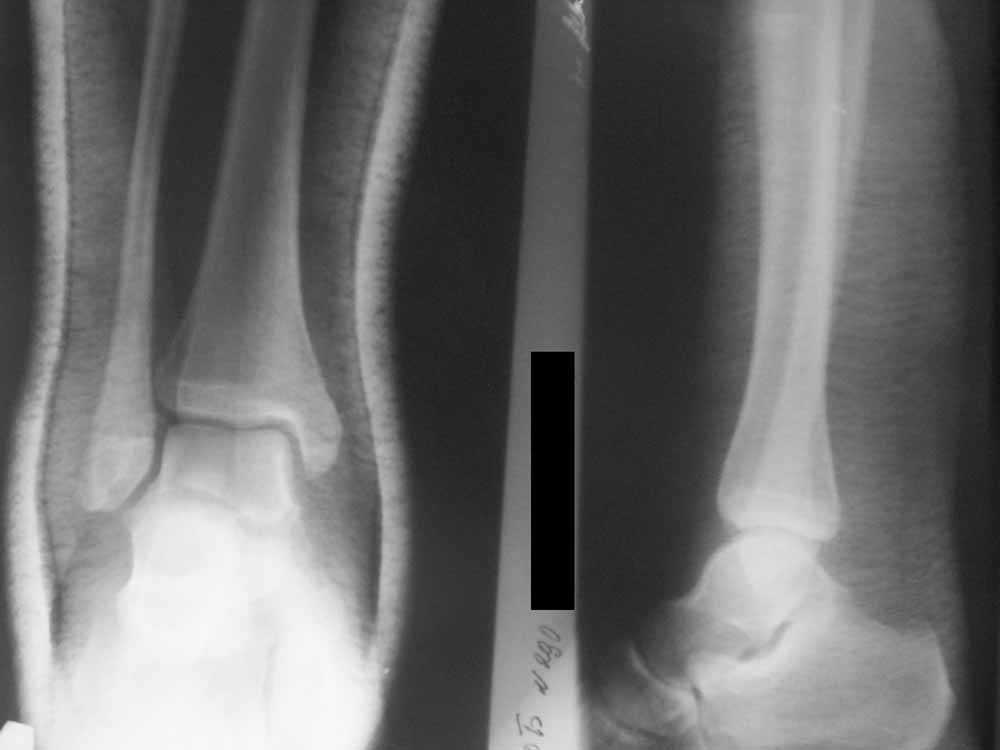

Уважаемые коллеги!Помогите, пожалуйста, советом! Пациентка 14 лет.

Двухлодыжечный

перелом с (как нам кажется) повреждением межберцового синдесмоза.

Вопрос один: оперировать или оставить "как есть" в гипсе? Не будет ли в

дальнейшем проблем с суставом. Заранее спасибо.